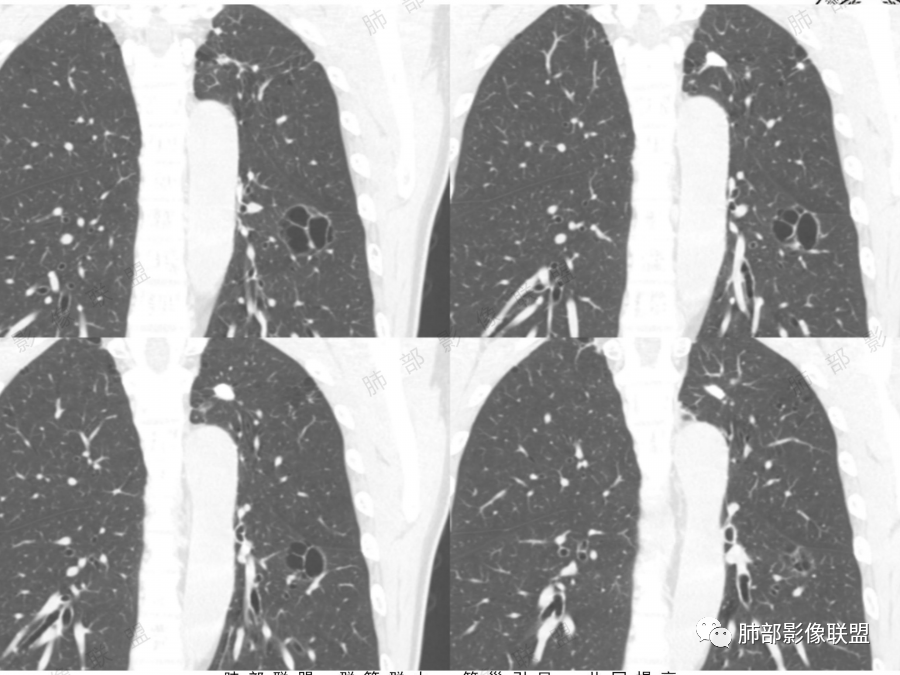

左肺下叶空腔,分隔状,壁厚薄不均,支气管截断,部分周围可见磨玻璃影,胸膜牵拉,左肺上叶多发结节,部分可见钙化,考虑1左肺下叶囊腔型腺癌。2左肺上叶结核。

中年男性,多发空腔,腔内可见分隔、壁结节。考虑:囊腔型腺癌。肺结核为陈旧性。

男51,体检发现肺部阴影,左肺下叶见多发薄壁囊腔影,可见结节,囊腔内见分隔,轻度胸膜牵拉,病灶周围少许磨玻璃影,常规考虑囊腔型腺癌,肿瘤标志物不高,除外结核。

中年男性,体检发现,吸烟史,但肺气肿背景不明显。左肺下叶囊腔病变,有一定张力,分隔明显,似有多个囊腔融合感,部分边缘见少许磨玻璃影,有支气管截断,首选囊腔型肺癌,某些先天病变(囊腺瘤样畸形等)也要考虑。

左肺上叶钙化结节,边界清楚,周围散在多发小结节,伴有磨玻璃影,考虑结核可能,左肺下叶多个囊堆积而成,大小不一,其内可见分隔,囊壁厚薄不均,病变近端与支气管相贴,支气管似扩张,考虑CCAM,鉴别囊腔性腺瘤,囊腔性腺癌

肺结核背景,左下肺簿壁囊腔,内有分格,有支气管截断,囊壁局限性增厚,嗜烟史,考虑左下囊腔型肺癌(鳞癌)。

左肺上叶陈旧肺结核,以增殖钙化灶为主,左肺上叶多发囊泡样结节,有分隔,稍分叶,周围少许磨玻璃,支气管部分截断,部分贴边穿过,老年男性,考虑囊腔型腺癌。

左肺上叶多发小结节影,部分钙化,考虑结核。左肺下叶多个囊状影,腔内见血管影,间隔稍粗大,考虑囊腔型肺癌,

老年,51岁男性病人,左上肺斑点,小结节状阴影,可见钙化,陈旧性肺结核改变,患者有长期的吸烟病史。左肺下叶背段多个囊腔肿块影,整体呈团块状类圆型,无明显壁结节,整体病灶张力较大,具备一定的膨胀感 ,支气管拉直并有突然截断改变,考虑囊腔型鳞癌。鉴别诊断:结核性病变,局限性囊性支气管扩张

男性,体检发现左肺阴影。影像表现:左上肺多发结节伴纤维条索影,部分钙化,左下肺囊腔样改变,内有分隔,部分分隔边缘见实性成分及GGO样改变,支气管从旁边经过,或受压,无明确进入依据。初步诊断:1、左上肺结核。2、左下肺囊腔型腺癌,诊断依据:分隔样囊腔,部分分隔有实变,边缘有GGO改变,鉴别诊断:1、囊腺瘤样畸形,分隔样囊腔要考虑,但部分分隔实变,部分伴GGO样改变成疑,最大的疑问是年龄51岁,体检发现,抽烟、饮酒30年,却无发病,可能性太小。2、囊腔性转移,单发分隔样囊腔转移少见,且需要病史支持。3、囊性淋巴瘤,一般以单发囊腔多见,分隔样囊腔型淋巴瘤罕见。4、感染,无相关临床症状及辅检支持,基本排除。

补充一下,虽然看到有GGO样改变,腺癌可能最大,但如果GGO是假像,有多年吸烟史,也不完全排除囊腔型鳞癌可能。

@傅昌瑜—贺州市人民医院—呼内 里面的血管进一步支持恶性。但不鉴别腺癌和鳞癌,主要鉴别的,还是多囊,张力较高,囊壁较薄(实变区除外),加GGO。